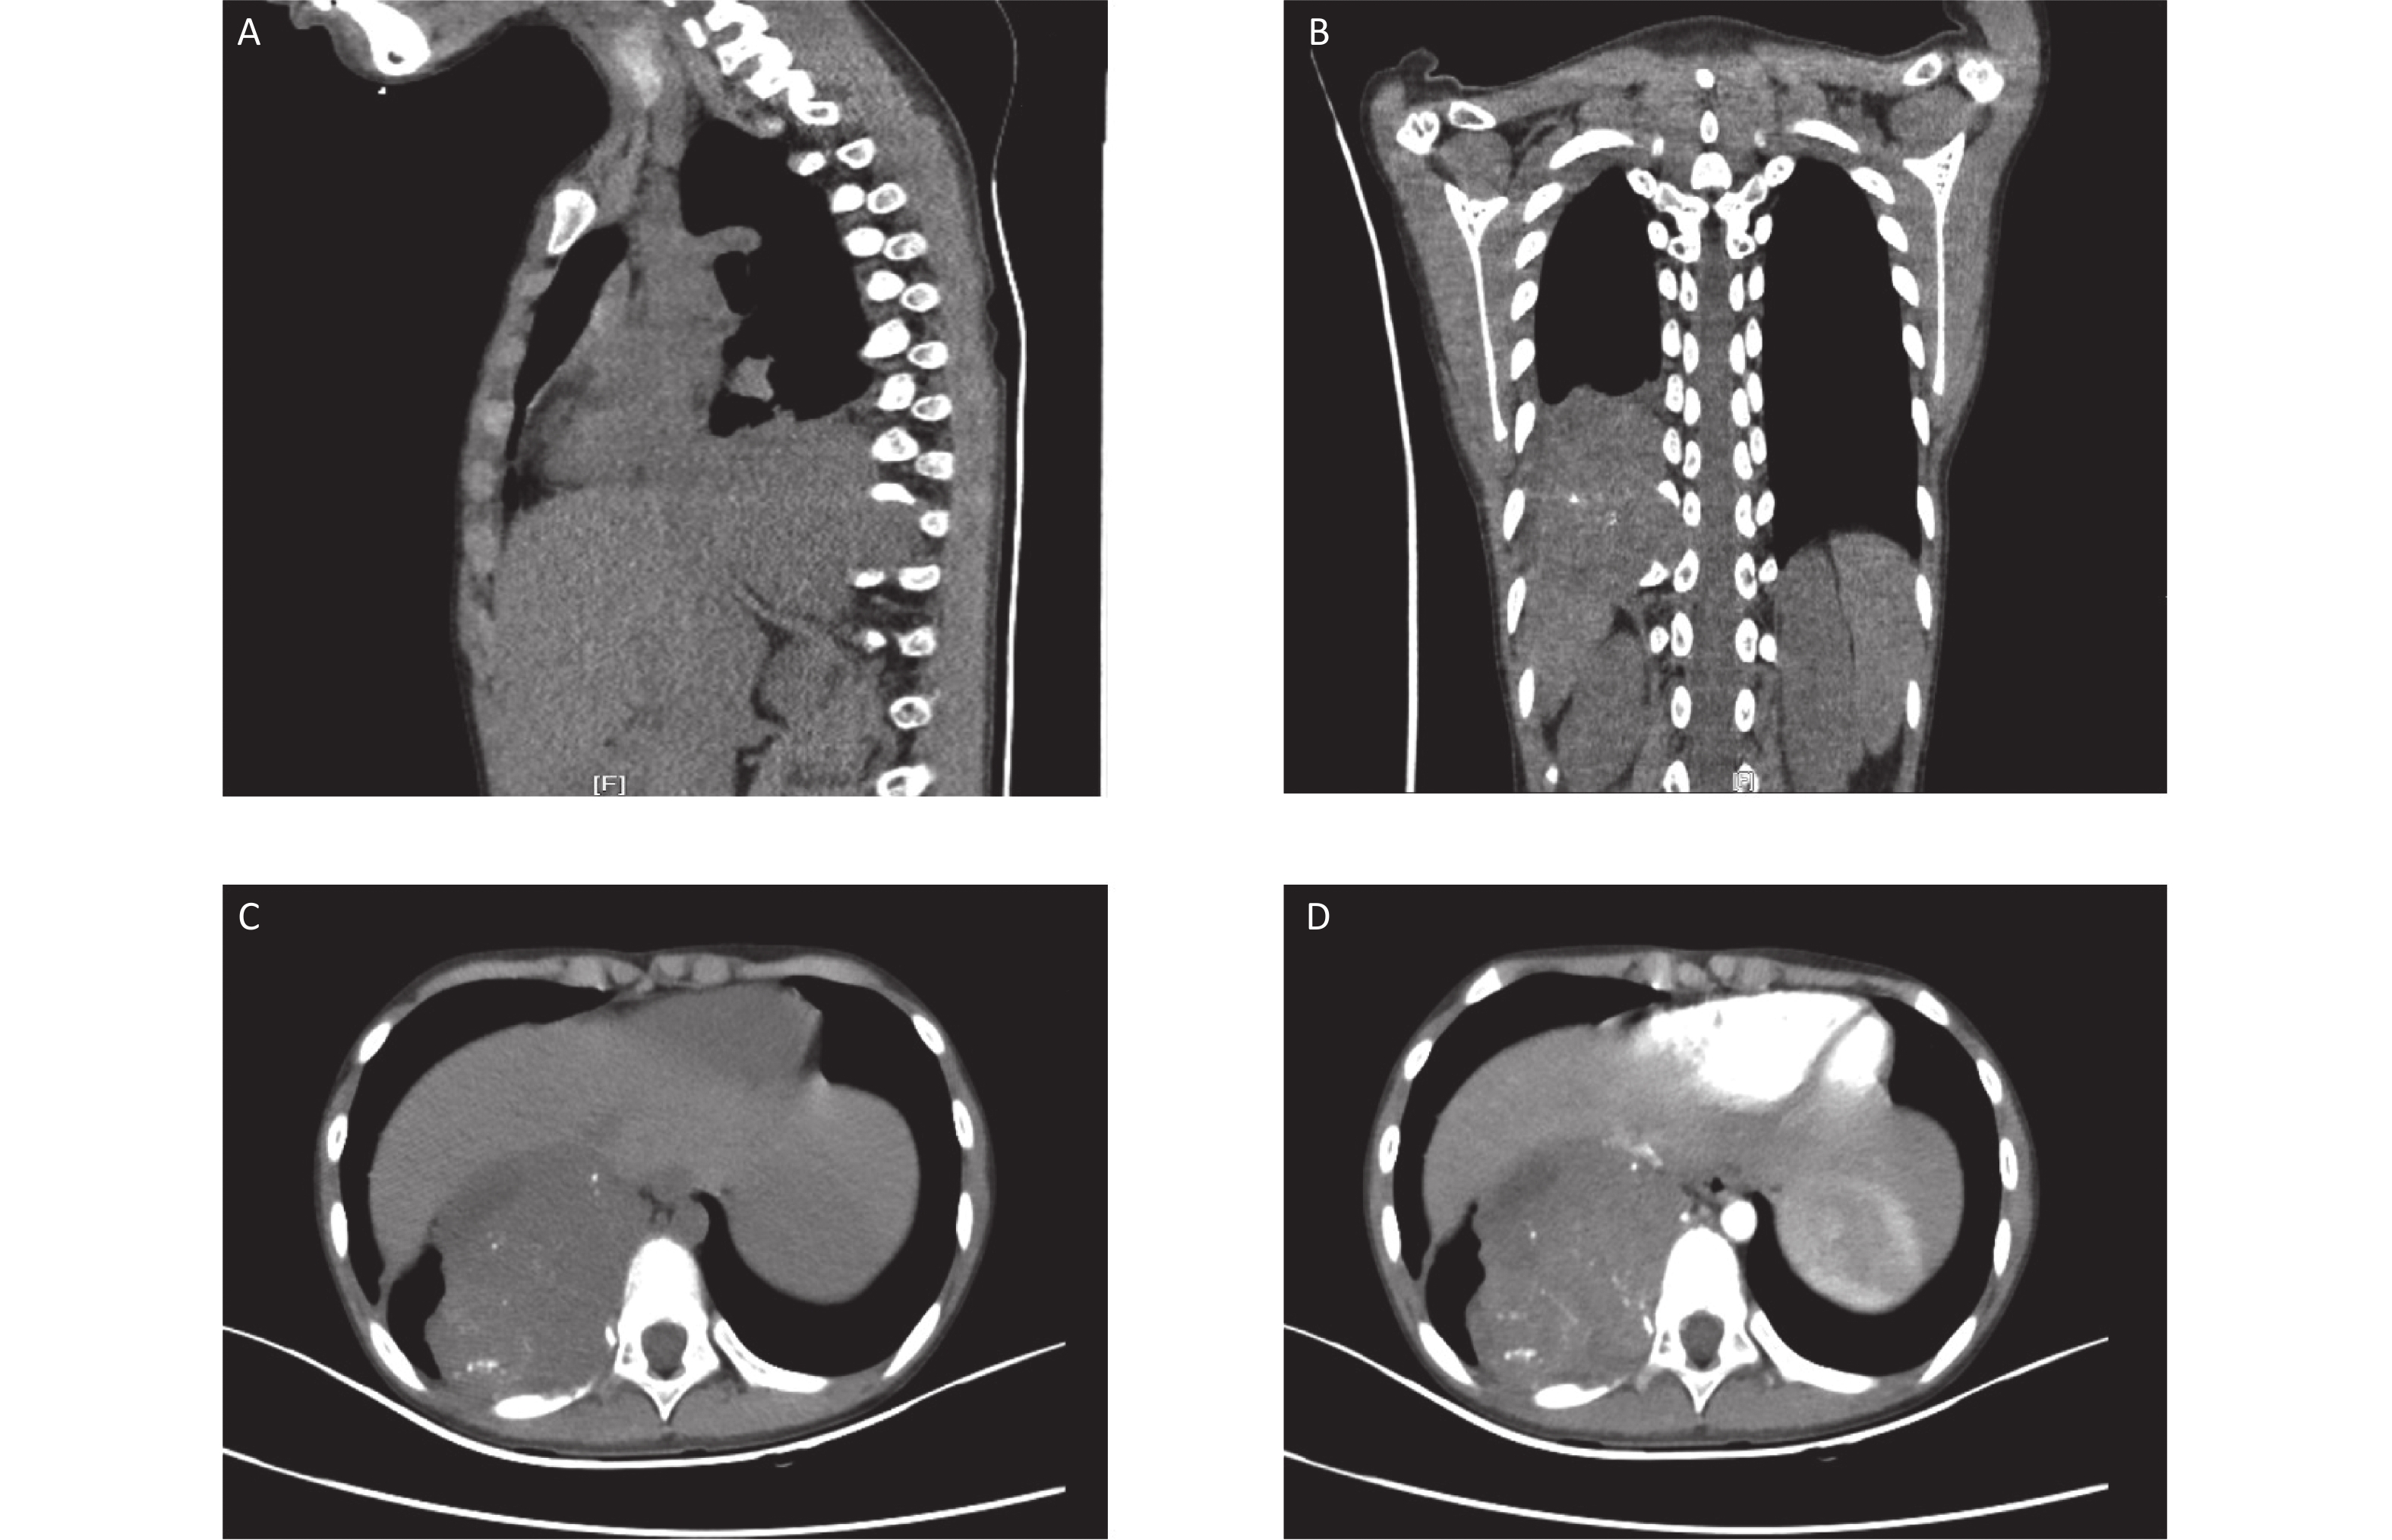

Here, we report a case of soft tissue ME in the mediastinum of a 9-year-old boy. A large heterogeneously enhanced soft tissue mass with multiple amorphous calcifications adjacent to the spine was detected in the right posterior mediastinum. The mass measured 7.3 × 5.9 × 7.4 cm3 and had infiltrated the tenth posterior rib (Figure 1). Immunohistochemical staining of the initial ultrasound-guided needle biopsy revealed positive expression for S-100, ERG, CD99 (locally), and Ki67 (3%) (Figure 2). Due to the invasiveness of the tumor, mesenchymal chondrosarcoma was the favored diagnosis, and one cycle of ifosfamide and doxorubicin was administered while the diagnosis was confirmed.

Figure 1.  Computed tomography (CT) images at the initial diagnosis. The three-dimensional CT scan showing a mixed density tumor expanding to the intervertebral foramina (A and B). Contrast-enhanced CT showing a large heterogeneously enhanced soft tissue mass with multiple amorphous calcifications in the right posterior mediastinum infiltrating the tenth posterior rib (C and D).